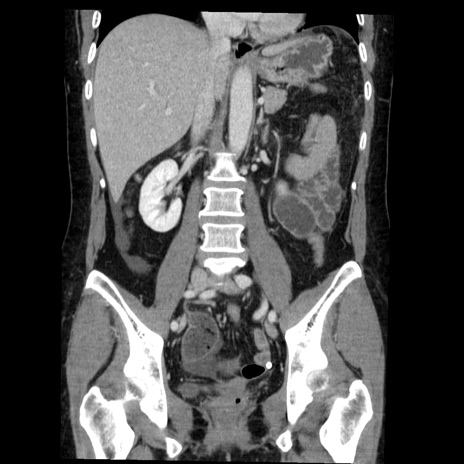

症例6(冠状断像)

【症例】50歳代女性

【主訴】下腹部痛

【現病歴】本日朝より下痢2回あり。 昼食を食べた後、嘔吐3回、下腹部痛認め、症状軽快せず、当院救急搬送。

最終食事:本日昼(生ものなし)。 昨日の夜、刺身を食ぺたとのこと。周囲に同様の症状の者なし。普段、排便は毎日あるとのこと。

【既往歴】卵巣癌術後(8年前に当院で卵巣摘出)

【身体所見】 意識清明、腹部:平坦、腸蠕動音→、やや硬、下腹部自発痛・圧痛あり、反跳痛あり、筋性防御なし。

【データ】WBC 16000、CRP 0.01